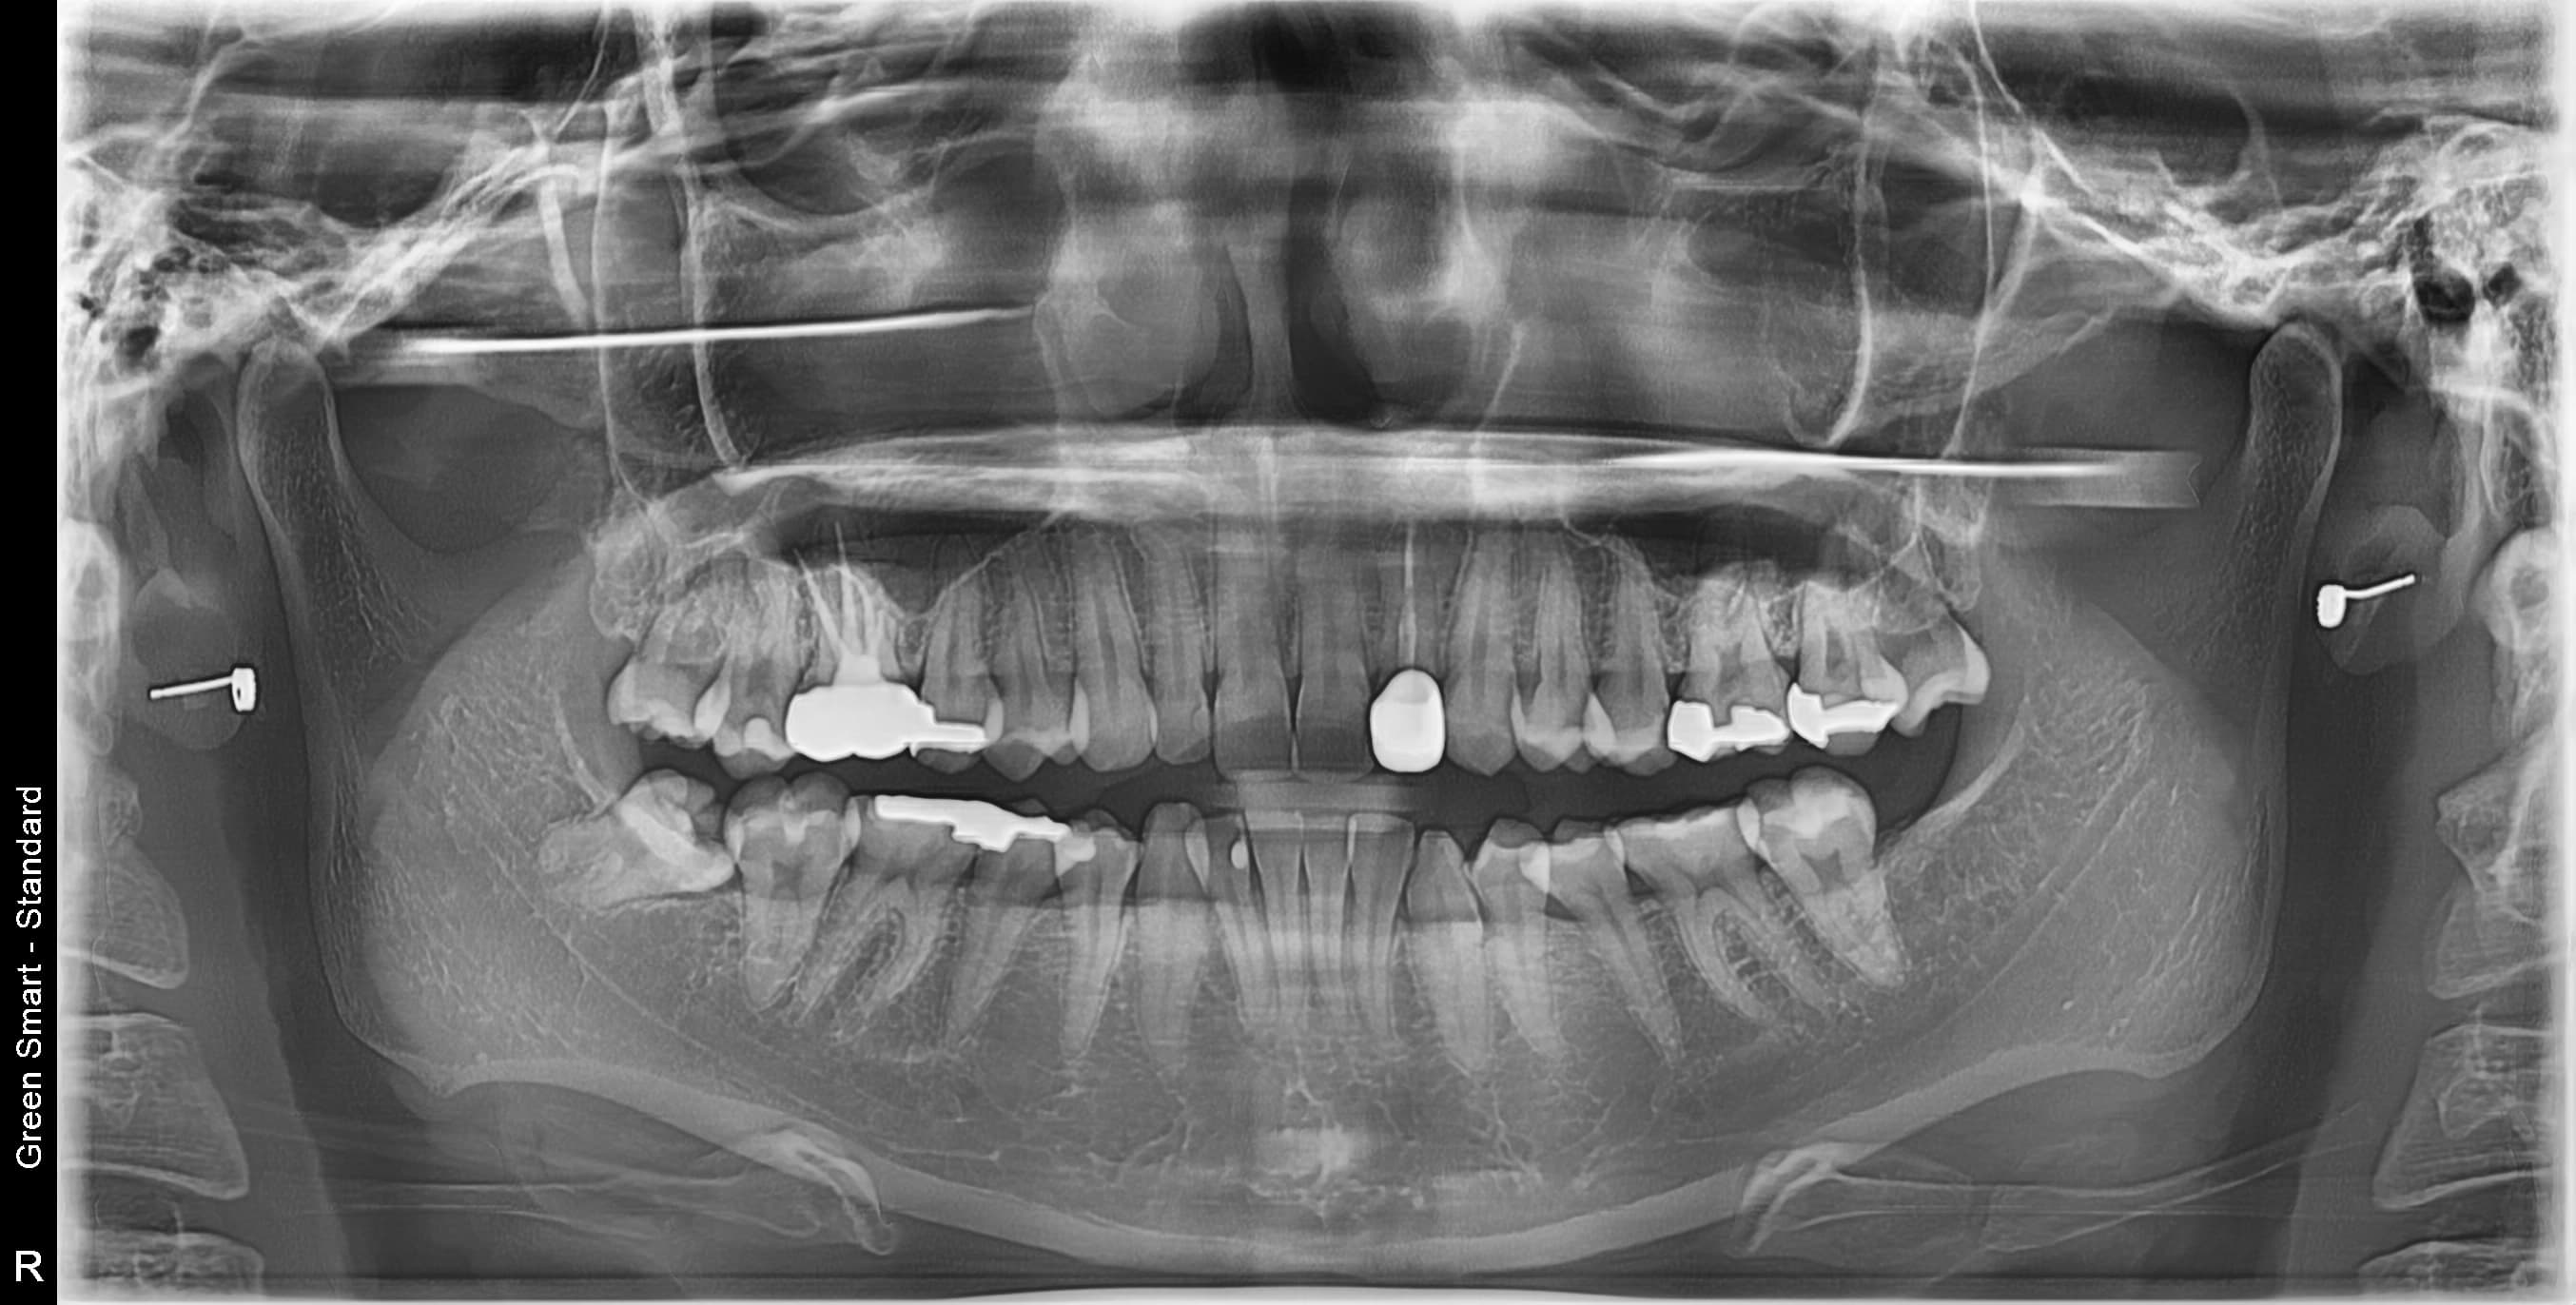

대학병원급 난이도 발치

일반 치과에서 "큰 병원 가보세요", "전문병원에서 빼세요" 이런 말 들어보셨나요?

복잡한 매복 사랑니 - 잇몸 속 깊이 묻혀있어도 OK

신경 근접 사랑니 - 신경 손상 걱정 없는 안전한 발치

수평 매복 사랑니 - 옆으로 누워있는 어려운 케이스도 가능

2,700건 이상의 발치 경험으로

대학병원 수준의 난이도도 안전하게 해결합니다

난이도 높은 사랑니도 뽑을 수 있나요?

네, 가능합니다. 경성 메디스 치과는 2,700건 이상의 발치 경험과 대학병원급 난이도 발치가 가능한 시스템을 갖추고 있습니다. 수평매복, 완전매복 등 일반 치과에서 큰 병원을 권유하는 어려운 케이스도 3D CT 정밀 진단으로 안전하게 발치합니다.